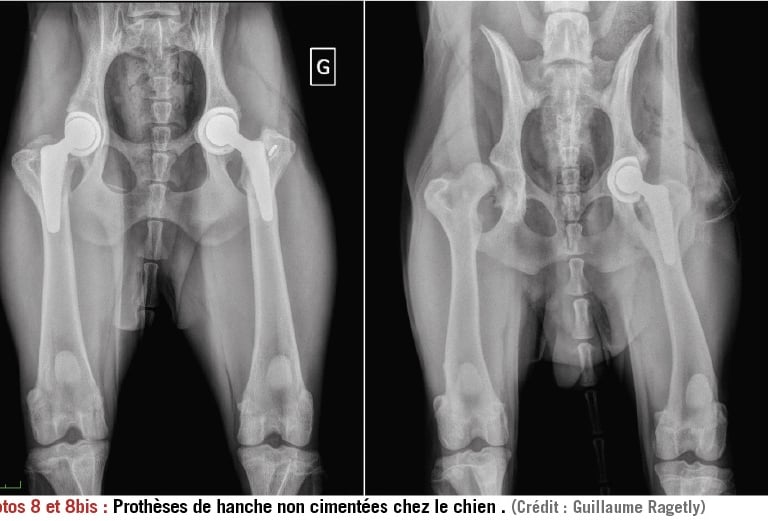

La chirurgie

Dans certains cas, la chirurgie constitue une solution palliative quand la douleur et l’arthrose sont trop importantes pour être gérer médicalement. Ainsi, une prothèse totale de hanche uni ou bilatérale peut être envisagée pour soulager une sévère arthrose coxo-fémorale avec un taux de réussite de 90% dans la reprise d’une activité normale si l’animal est ramené à un poids de forme. Les autres chirurgies palliatives les plus courantes sont les prothèses de genou ou les arthrodèses qui consistent à « fixer » une articulation devenue trop douloureuse. Le principal frein à cette solution est le coût très élevé de ces interventions spécialisées.

Prothèses totales de hanches.

copyright Dr Ragetly CHV frégis